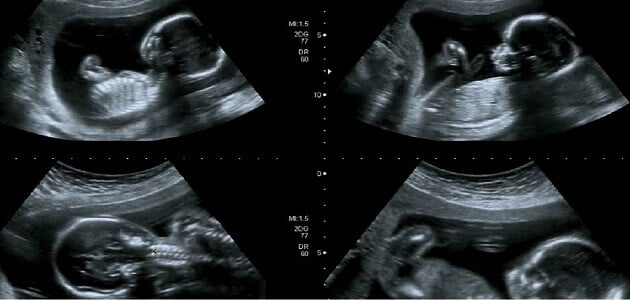

متى يظهر نوع الجنين وطرق الكشف الأبرز لعام 2022 هذا ما سأقدمه لك عزيزي القارئ على موقعنا في الكبسولة مع ذكر أفضل طرق الكشف عن نوع الحمل بكل سهولة